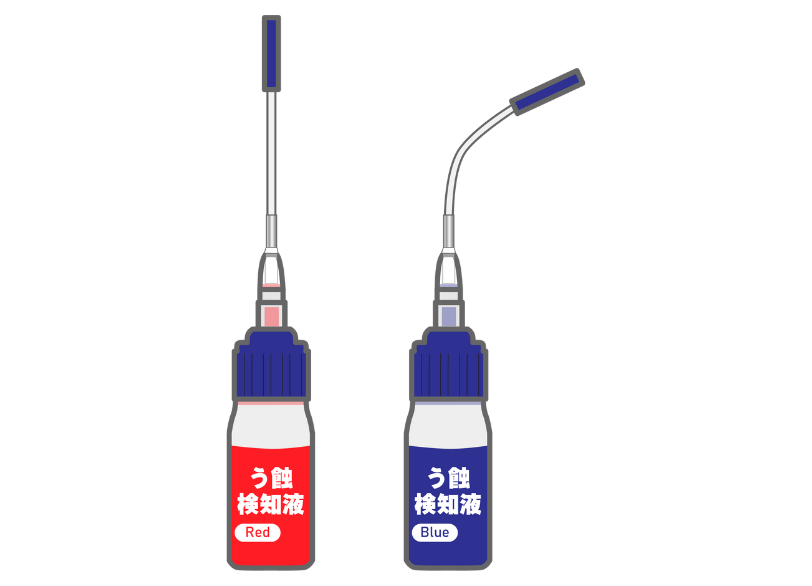

特殊な薬剤による虫歯の可視化

虫歯の部分と健康な部分の境界は肉眼では判別が難しい場合があります。

当院では必要に応じて「う蝕検知液」という虫歯に感染した部分だけを赤く染め出す特殊な薬剤を使用します。

これにより削るべき範囲を正確に見極め、健康な歯を削りすぎてしまうリスクを防ぎます。